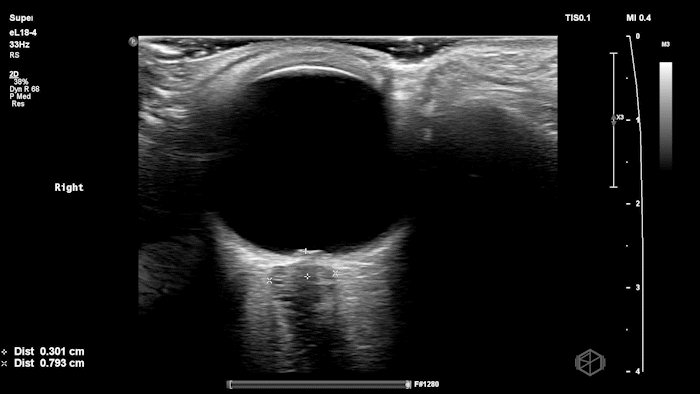

They were examining a 30’s female who was presenting to the ED with headaches for multiple years and had some vision disturbances. The performed an ocular POCUS that demonstrated the following:

The POCUS shows optic nerve edema right (0.793cm) greater than left (0.71cm) with bilateral papilledema. There may also be a faint vitreous detachment of the right eye. There was concerned for increased intracranial pressure.

The patient had an MRI brain and orbits that showed, “intraocular protrusion of the right greater than left optic nerve heads with increased prominence of the CSF spaces of the bilateral optic nerve sheaths, can be seen in a idiopathic intracranial hypertension.” She had a lumbar puncture that had elevated opening pressure and was started on acetazolamide.

Diagnosis: Bilateral optic nerve edema/papilledema and idiopathic intracranial hypertension

ONSD measurements in this case are markedly abnormal. The optic nerve sheath diameter (ONSD) is measured 3 mm posterior to the globe. In adults, an ONSD > 5.0 mm is generally considered abnormal; values > 6.0 mm are strongly associated with raised intracranial pressure (ICP). Bilateral measurements of 7.9 mm (right) and 7.1 mm (left) are consistent with elevated ICP. The probe should be held lightly with ample gel to avoid artifactual compression (📚 PMID: 18509619, 18275454)

Point-of-care US measurement of optic disc elevation/height helps when fundoscopy is limited. Studies report cutoffs from ~0.6–1.0 mm: ≥1.0 mm is highly specific for papilledema in ED cohorts; lower cutoffs (≈0.6–0.7 mm) improve sensitivity. (📚 PMID: 24050798, 37227512)